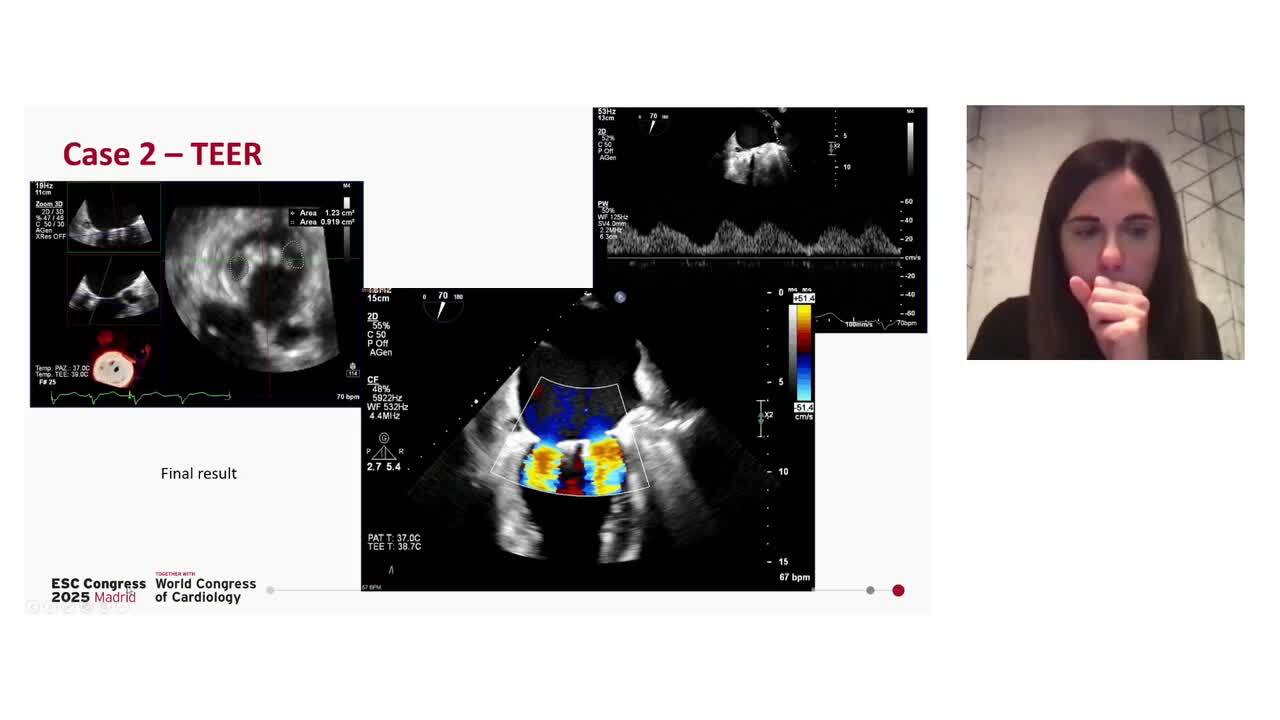

Case 2: simultaneous diagnosis of dilated cardiomyopathy and secondary mitral regurgitation

Congress Presentation

31 Aug 2025 - 18:35